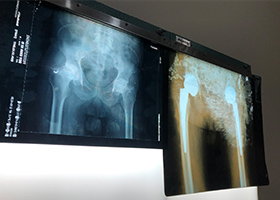

2 Year Follow Up Bilateral Hip Cambodia 2 Year Follow Up Bilateral Hip Cambodia 2 Year Follow Up Cambodia Bilateral Hip 2 Year Follow Up Cambodia Bilateral Hip 2 Year Follow Up Cambodia Bilateral Hip 2 Year Follow Up Cambodia Bilateral Hip